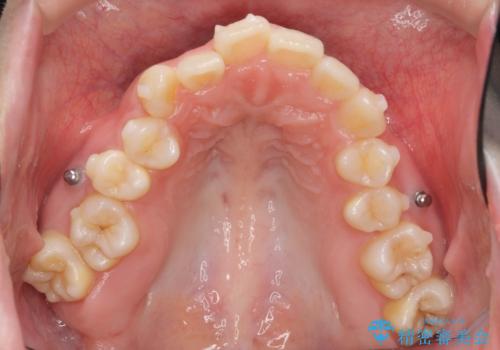

口腔内の清掃状態の良さに加えて、マウスピースを毎日きっちりと装着し、しっかりと使用していただけたことからワイヤー矯正は行わずにきれいに歯並びを治すことができました。

途中顎位が変わり、マイクロインプラントを併用した上顎臼歯の遠心移動が必要となったため治療が長期化しました。